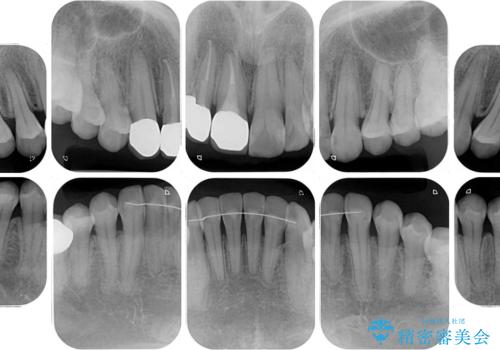

- 前歯の歯並びやむし歯治療の跡、奥歯の銀歯を気にして来院された患者様です。

インビザラインによる矯正治療の後に虫歯や銀歯をセラミックにて補綴することとしました。

前歯のむし歯治療の跡や奥歯の目立つ銀歯がなくなり、明るい口元になりました。